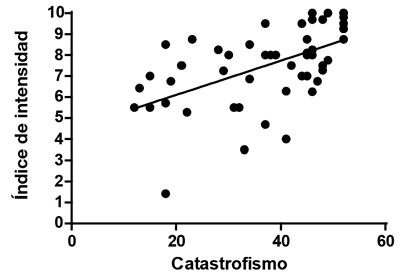

Se encontró una correlación lineal positiva moderada y estadísticamente significativa (R = 0,49, p = 0,0003) entre el valor de EVN y el catastrofismo total, una correlación lineal positiva moderada y estadísticamente significativa (R = 0,54, p < 0,0001) entre el índice de intensidad del dolor y el catastrofismo total (Figura 3), y una correlación lineal positiva moderada y estadísticamente significativa (R = 0,4, p = 0,004) entre el índice de interferencia del dolor y el catastrofismo (Figura 4).

Fig. 3. Correlación entre índice de intensidad y catastrofismo total. Esta correlación es positiva y moderada, estadísticamente significativa.